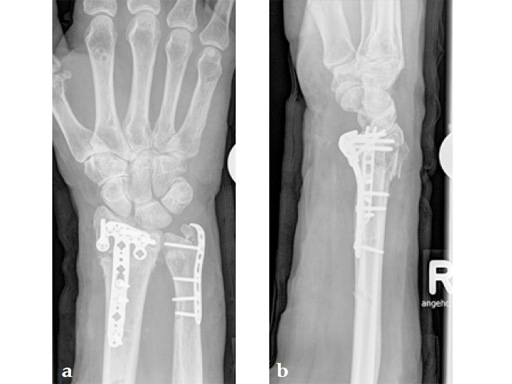

Fig 4ab X-rays 3 days postoperatively: removable splint, early motion with physiotherapy.